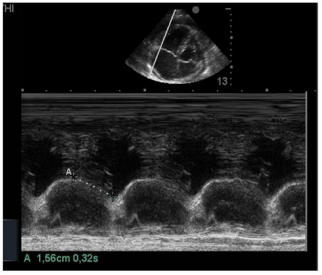

Na insonação cardíaca beira-leito, a mensuração da excursão do anel da tricúspide (TAPSE) resultou em 1,56 cm como demonstrado na imagem apresentada. Isso significa ventrículo direito